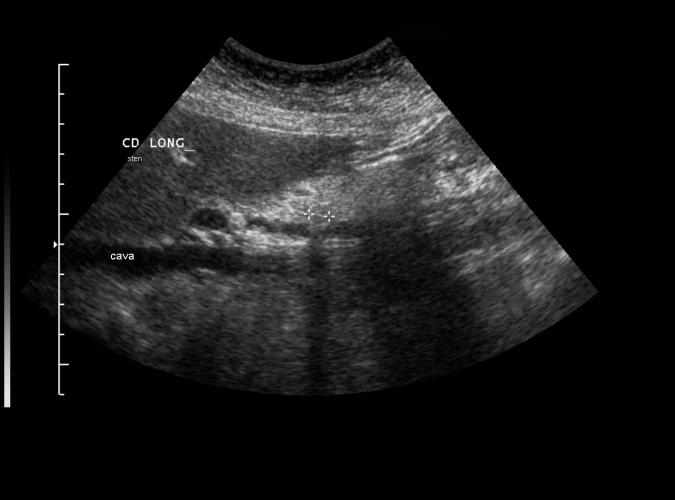

Post cholecystektomi patient. Normalvid gallgång i leverhilus (8a)...ändå choledochuskonkrement. Konkrement mellan kryssen. ERCP bekräftar.